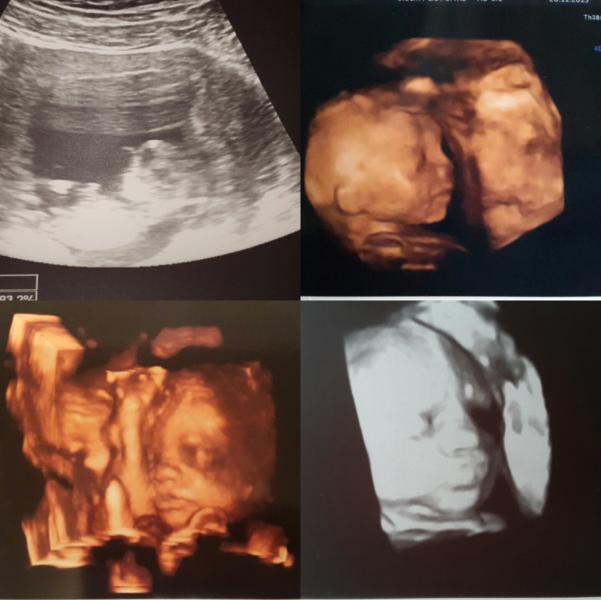

ИСТОРИЯ нет нет 😂 не родов (на них мой сын еще не созрел) ,а моей БЕРЕМЕННОСТИ 😉

Все началось в августе месяце , задержку я заметила слишком поздно , из-за сбившегося в очередной раз цикла и в аптеку за тестом я побежала ,когда меня стало тошнить от мяса ,что мне не свойственно совершенно 😒

Раз тест , два тест , на обоих 2 яркие полоски ...😰

Я глазам своим поверить не могла 👀 , до этого полгода стараний в пустую подкосили мою надежду на лялечку , но вот так неожиданно Бог ис...